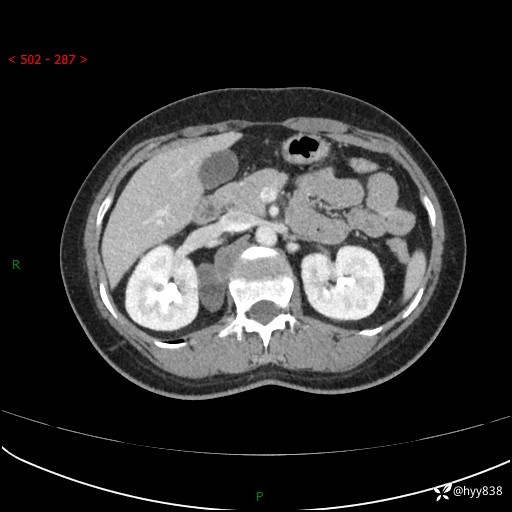

现在都流行跨界,病变也不例外,从腹膜后长到胸腔了---结果公布~

主诉:体检发现右侧腹膜后肿物1天

简要病史:患者于1天前因体检发现右旁肾占位,无肉眼血尿,无畏寒发热,无咳嗽咳痰,无腰腹部疼痛不适,无尿频尿急症状,起病来,患者未行特殊治疗,为求进一步诊治,门诊以"右侧腹膜后肿物"收治入院。 发病来患者精神、饮食、睡眠良好,小便如上,大便正常,体重无明显变化。

临床诊断:腹膜后肿物

上腹部CT增强(动脉期+实质期)(外院平扫)